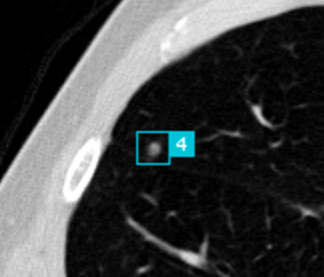

Screening of high risk groups could potentially increase early detection and thereby improve the survival rate [5; 6]. However, the (cost-) effectiveness of screening would be largely dependent on the skill, alertness and experience level of the reading radiologists, as potentially malignant lesions are easy to overlook due to the rich vascular structure of the lung (see Figure 1). A way to reduce observational oversights would be to use second readings [7; 8], a practice in which two readers independently interpret an image and combine findings, but this would also drastically add to the already increasing workload of the radiologist [9], and increase the cost of care. Thus, a potentially much more cost-effective and accurate approach would be to introduce computer aided detection (CAD) software as a second reader to assist in the detection of lung nodules [10; 11].

All scans from the NLST and LIDC/IDRI datasets with an original slice thickness equal to or less than 2.5mm were processed by the same candidate generation model to provide center coordinates of potential nodules. These center coordinates were used to extract patches from the original scans, where each voxel represents mm of lung tissue. Values of interest for nodule detection lie approximately between -1000 Hounsfield Units (air) and 300 Hounsfield Units (soft-tissue) and this range was normalized to a range.